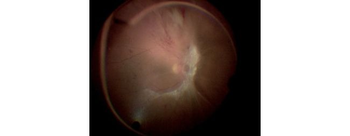

Le décollement de la rétine survient le plus souvent à la suite d’un décollement postérieur du vitré. Ce mouvement peut entraîner la formation de déchirures rétiniennes par traction. À partir de ces déchirures, du vitré liquéfié peut s’infiltrer sous la rétine et provoquer un décollement.

Les principaux facteurs de risque sont :

• La myopie,

• Un antécédent de chirurgie de la cataracte,

• Un traumatisme oculaire.

Cette situation nécessite habituellement une prise en charge rapide afin d’éviter l’atteinte de la zone centrale de la rétine.

Plusieurs techniques chirurgicales sont possibles :

• Indentation sclérale (chirurgie externe) : réapplication de la rétine par déformation de la paroi de l’œil ;

• Vitrectomie : retrait du vitré et réapplication interne de la rétine.

Lors d’une vitrectomie, un gaz expansif est fréquemment utilisé en fin d’intervention. Sa présence dans l’œil contre-indique les voyages en avion durant les trois semaines postopératoires